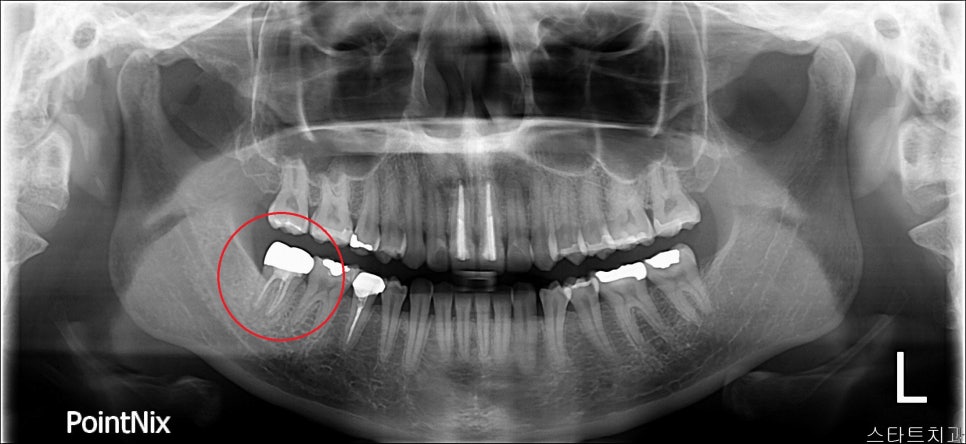

재식_ 후 x-ray

위 사진은 이식 직 후 사진입니다. 이식 전 x-ray 사진과 비교해보시면 뿌리끝에 충전된 모습이 보이실 겁니다.

재식_전 파노라마 재식_후 파노라마

이렇게 이식된 치아는 주변 잇몸뼈와 치아가 잘 붙기를 기다려야 합니다. 임플란트와 마찬가지로 3-4개월 정도 기다려야 합니다.